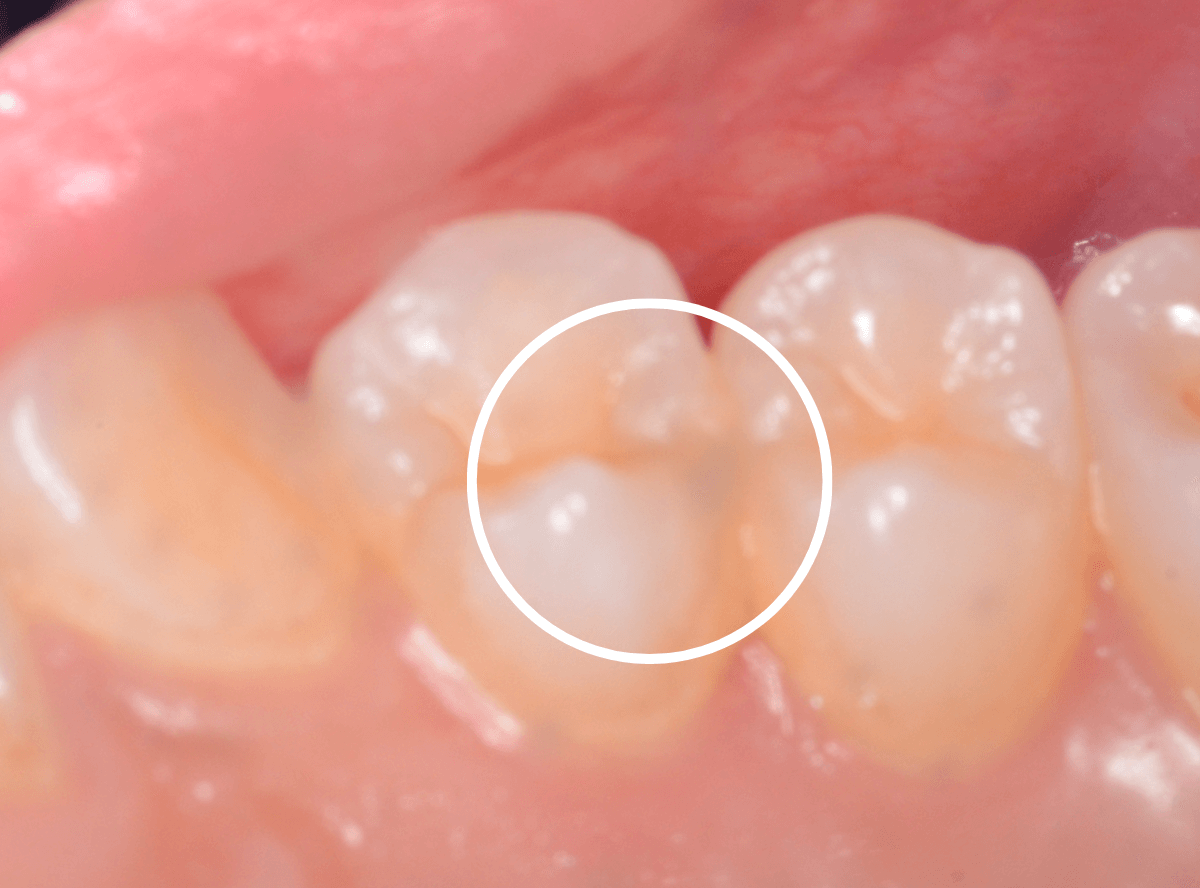

角度を変えてみたところです。

ちょっと黒っぽいところが見えますね。